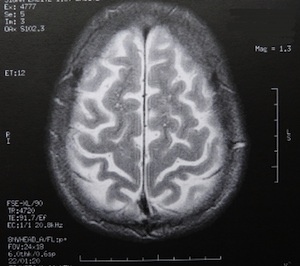

Das menschliche Gehirn verfügt über enorme "Rechenpower". Bild: pixelio.de/Dieter Schütz